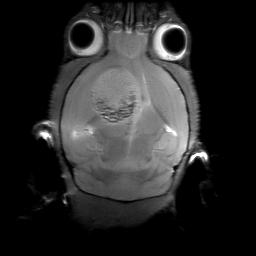

MRI image of brain tumor